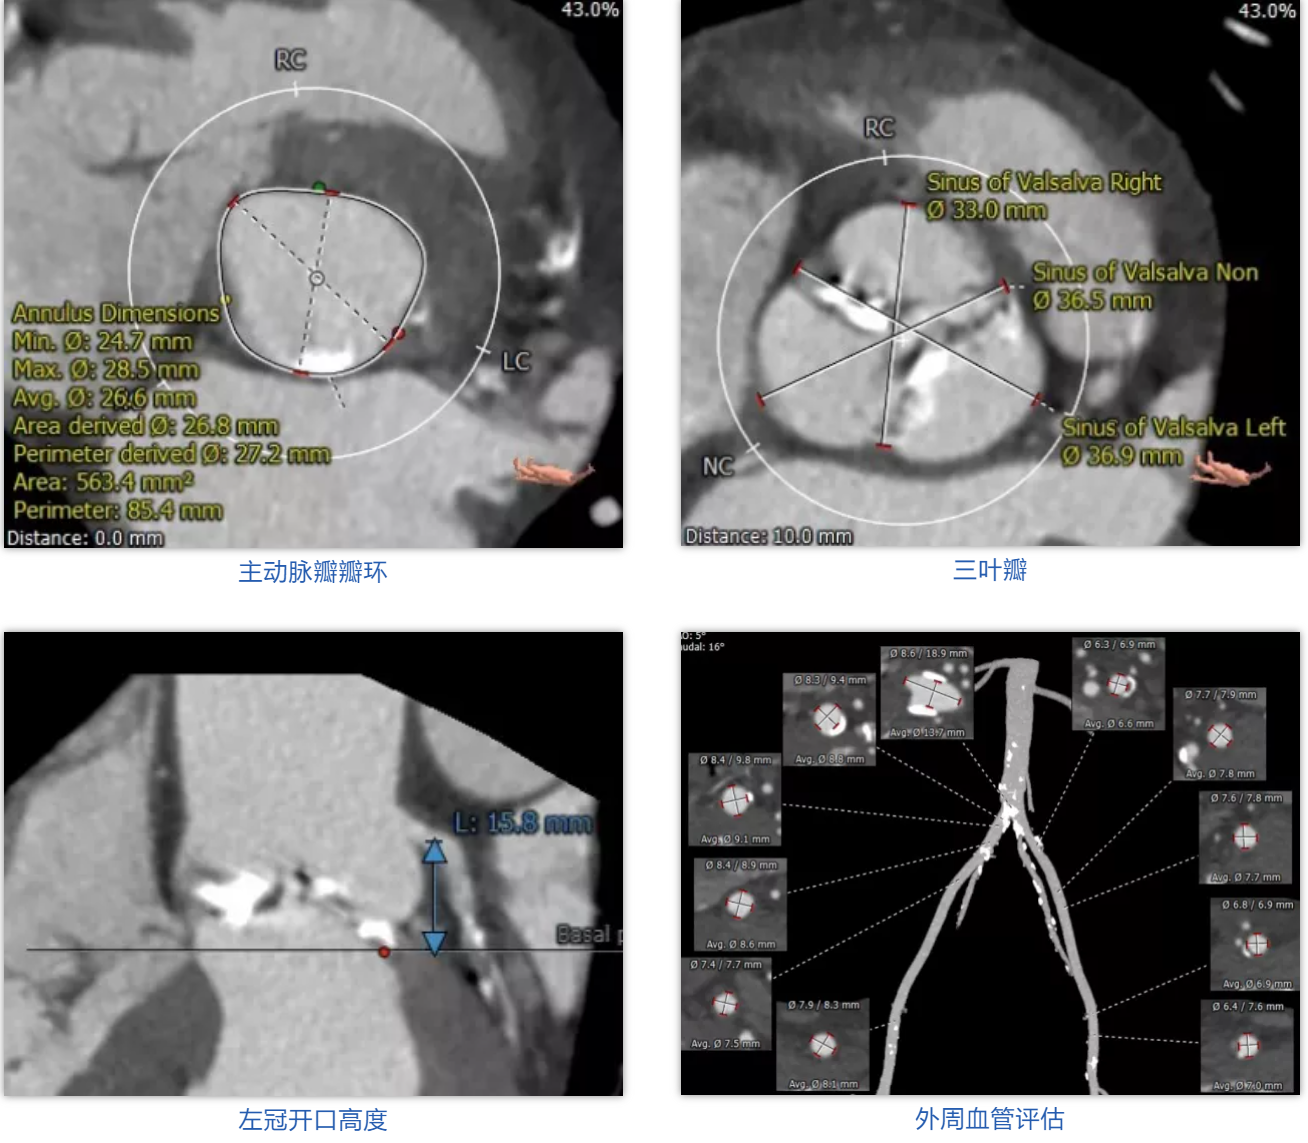

患者男性,69岁,主因“活动后胸闷、憋气1年余”入院,术前心脏超声提示主动脉瓣瓣叶钙化,重度狭窄,轻度反流。患者STS评分9.5%,属于常规外科换瓣手术高风险。CT评估结果显示主动脉瓣为三叶瓣,瓣叶钙化,瓣环平均直径26.6mm,瓣环面积563.4mm2,面积径26.8mm。左冠脉开口高度15.8mm,右冠脉开口高度17.3mm。术前经详尽影像学重建、评估及病例讨论,测量瓣环直径,评估冠脉梗阻风险后,计划植入 27# Renatus介入主动脉瓣。

外周血管评估